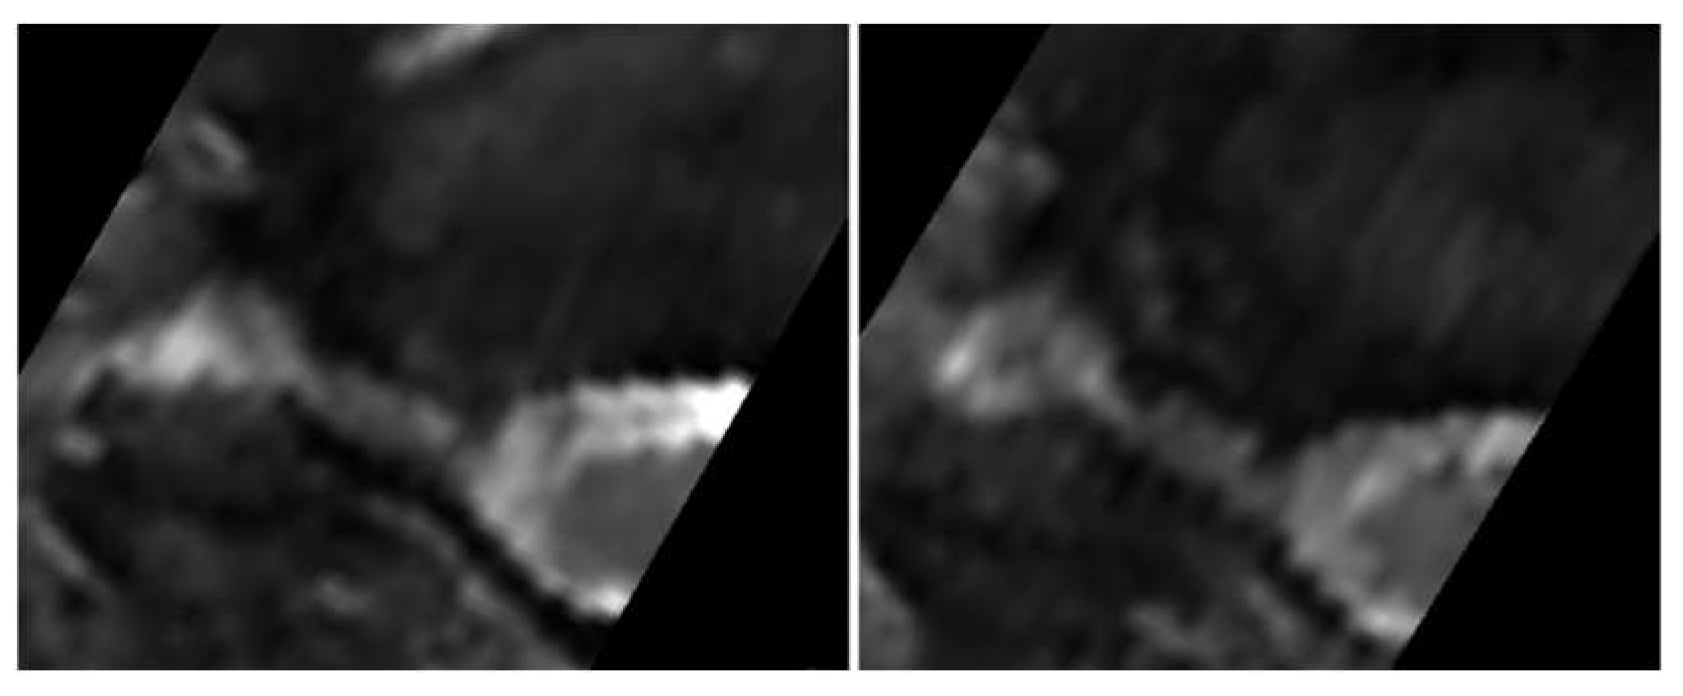

All patients were positioned without any complaints in the DMRICS apparatus, outside the MRI gantry. The patients were subsequently positioned within the MRI for a relaxed image acquisition. After successfully conducting the simulated Spurling test, immediate imaging was performed, which produced clinically acceptable image quality in 9 out of 10 patients in both relaxed and provoked positions, as shown in Figure 2 and Figure 3.

The significant increase in the qualitative gradings of the foramina when comparing MRI before and during the simulated Spurling test indicates that a Spurling test leads to higher Park and Kim grades. This offers not only insights into the variations of the often-employed clinical Spurling test but also suggests a possible clinical utility for dynamic MRI. The method could help in determining the severity of foraminal stenosis and identifying the impacted nerve roots if they are not distinctly discernible in a routine, relaxed MRI, especially when several foramina are narrow on a routine MRI and the symptoms and clinical examination cannot discriminate which nerve root(s) are giving rise to the experienced pain. However, for the foraminal area and cross-distance measures, no significant changes were detected in the present work. The reason for these contradictory findings may be that the foraminal shape shifts with compression and thereby the nerve compression may increase, even if the overall area is not changed or even increases; see Figure 2 and Figure 3. Further, the magnitude of measurement error in such small structures, especially for the axial-cross-distance measurements may also play a role here.

Figure 2. The upper (left) image depicts an oblique image in a relaxed position compared with the (right) image taken during the Spurling test. The foraminal areas are marked in the lower pair of images.